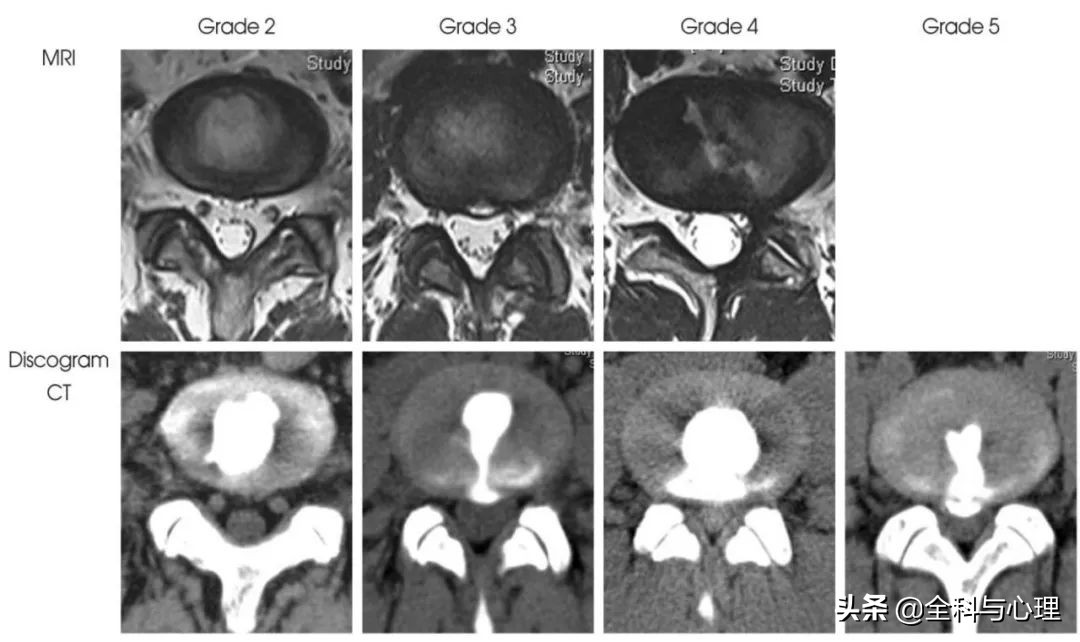

椎间盘破裂分级 MRI 及造影后 CT 示意图

Peng 等的研究显示,椎间盘造影术后 CT 上表现的纤维环撕裂,是自髓核到纤维环后方的肉芽组织条带区内,存在丰富的 P 物质 (SP) 和神经丝蛋白 (NF) 阳性神经。SP 阳性神经纤维具有伤害传入性,当造影剂由髓核向后方流出纤维环外层时,注射产生的压力作用于肉芽组织中的神经纤维,产生腰痛复制。随着造影剂流出纤维环,椎间盘内压力消失,疼痛随之减轻。提示椎间盘后方神经分布广泛的肉芽组织条带区是椎间盘源性腰痛的起源部位。